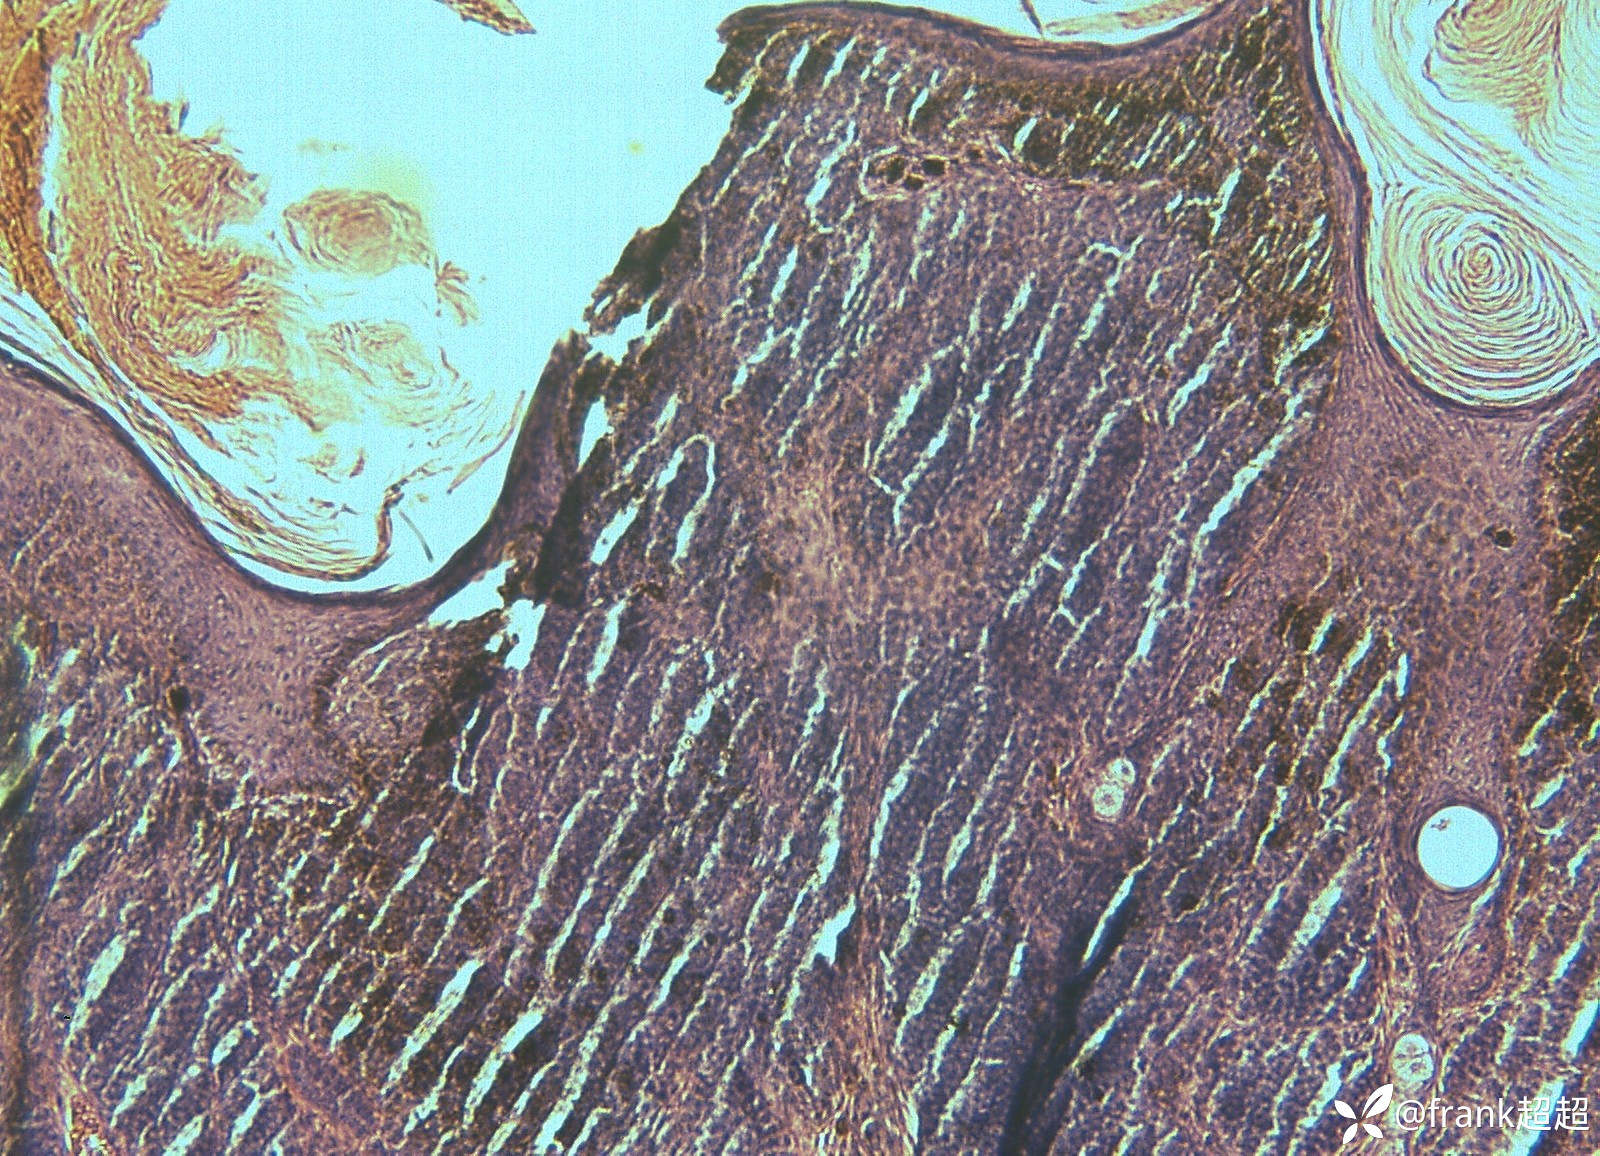

病理提示:表皮角化过度,棘层轻度增生,表皮突下延,基底层及真皮内痣细胞成巢及散在分布,围绕附属器排列,有成熟现象,真皮上部痣细胞含黑素颗粒。